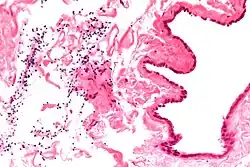

| Ultrasound of a testicle (grey) and a spermatocele (black). | |

The primary care physician may diagnose and manage benign causes of scrotal masses such as hydrocele, varicocele and spermatocele. However, if a "must not miss" diagnosis related to testicular masses such as testicular torsion, epididymitis, acute orchitis, strangulated hernia and testicular cancer is suspected, the family physician must refer to a urologist.[19] Finding a painless, cystic mass at the head of the epididymis that is clearly separate from the testicle can indicate a spermatocele. Shining a light through the mass, a process known as transillumination, can also help differentiate between a fluid-filled cyst and a tumor, which would not allow as much light to pass.[20] If uncertainty exists, ultrasonography of the scrotum can confirm the presence of a spermatocele.[7] The location and history of any scrotal masses are crucial in determining whether or not the mass is benign or malignant.[21] Lab tests such as a complete blood count (CBC test) or urine test can also be conducted to check for any possible infection or signs of inflammation.[22]

Spermatoceles come in varying sizes and shapes. Some spermatoceles are very small and can only be detected through an ultrasound. More commonly seen are spermatoceles that are a pea-sized lump. They tend to form above or behind a testicle and have a shape and size that looks like a pea. Larger growths have been reported to look similar to a third testicle and can be very discomforting.[22] For those who are affected with large spermatoceles, some have reported feeling pain, heaviness, and fullness in the affected testicle.[20]

Although the evidence and information for incidence of spermatoceles in children is lacking, there are general management guidelines for caregivers who may encounter spermatoceles in their children.[9] Epididymal cysts are typically benign in nature. However, caregivers should take note of any discomfort and symptoms in children, including but not limited to, erythema, scrotal edema or swelling.[9] Epididymal cysts appear in approximately 70% of boys who present as asymptomatic.[9] The diagnosis of epididymal cysts in children can be discovered upon physical examination and eventually confirmed via ultrasound.[9]

Upon physical examination, if a 'lump' is found during the testicular exam, further screening may be performed via ultrasound to eliminate testicular cancer.[18]